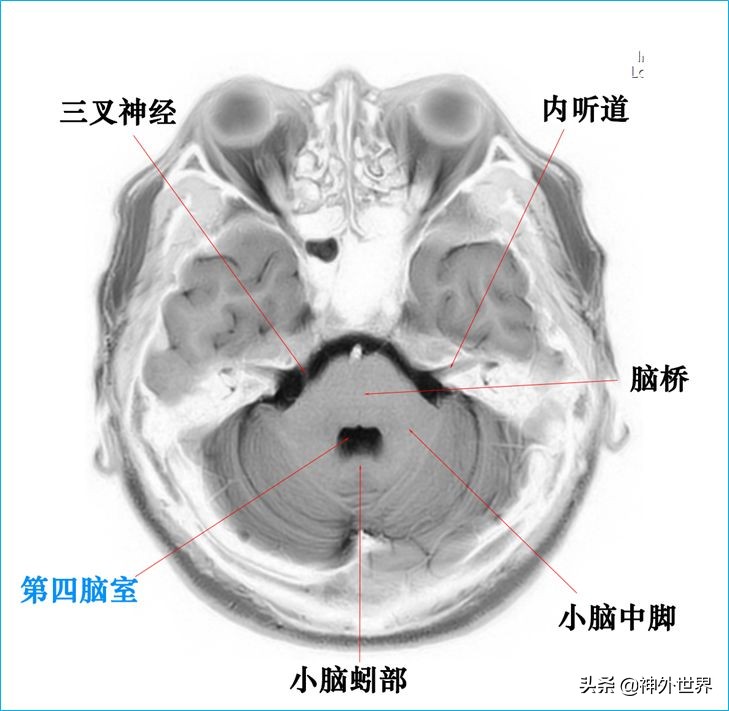

四、T2WI反相图学颅脑断层解剖

以下图片均来自我院3.0T核磁共振的T2WI反相图。标注均为我自己完成,水平有限,难免有误,还望各位老师多多指正。谢谢。

参考书目: 《imaging of the brain》《Applied Cranial-Cerebral Anatomy 1stEdition》